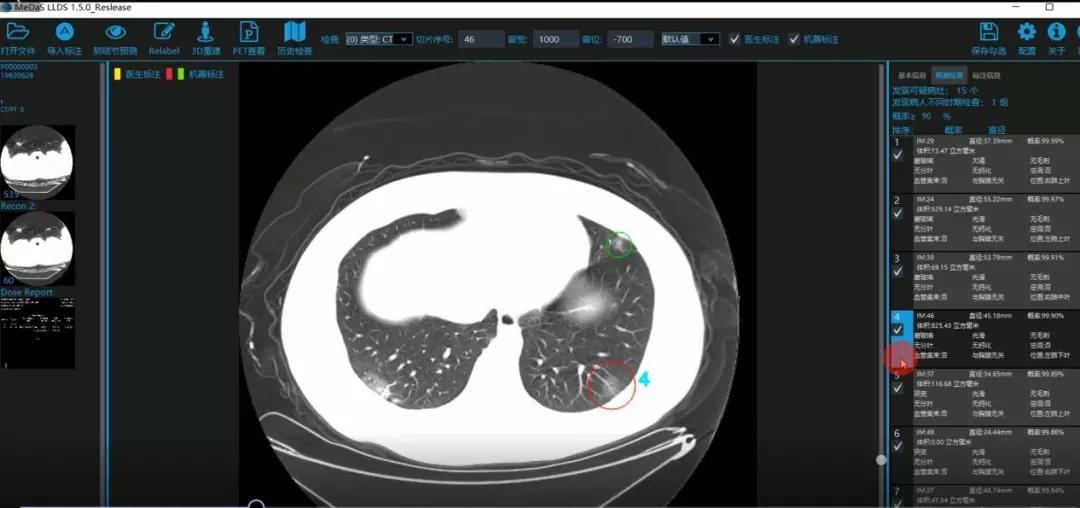

医护人员的好帮手:基于深度学习的新冠肺炎早期检测筛查系统

西电必赢242net官网智能软件与系统新技术研究所副教授张亮的爱人是西安交通大学第二附属医院抗疫一线的影像科医生,疫情发生以来,他们讨论最多的就是新型冠状病毒感染者的早期诊断问题。作为一名医护家属,身为高校科研工作者,张亮深知快速准确地诊断新冠肺炎早期患者对控制和防治疫情的重要性和挑战性。他与团队成员主动出击,通过远程网络会议,在前期医学影像处理的研究基础上加速科研攻关,反复讨论方案,屡次设计模型,与上海宽带技术及应用工程研究中心、上海交通大学医学院附属瑞金医院等合作单位的人员多次标注整理患者肺部CT影像数据到深夜。与此同时,他们依托上海瑞金医院、西安交通大学第二附属医院等的新冠肺炎疑似、确诊患者肺部CT影像,通过综合分析新冠肺炎患者的肺部CT影像特点(磨玻璃、体积大小、位置等特征),张亮团队加快技术攻关,设计开发了基于深度学习的新型冠状病毒的早期检测筛查模型系统。

对应新冠肺炎CT病灶检测效果

令人欣喜的是,通过对实际门诊数据排查测试,该模型可以减轻医护人员近80%的工作量,新冠肺炎患者的检测召回率超过95%。目前,模型系统正在进行最后的调试工作,很快投入到“战疫”一线,缓解医护人员紧缺、确诊检测工作耗时较长等问题,减少医护人员的工作时间和劳动强度,提高工作效率。